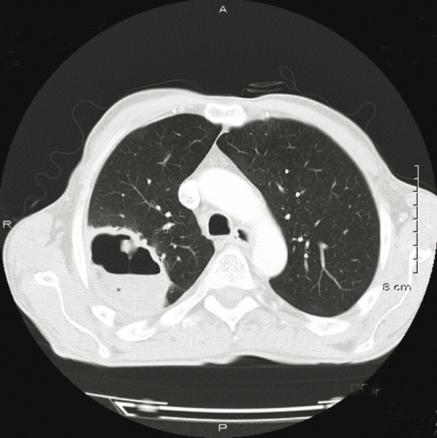

Abcès pulmonaire

TDM thoracique. Abcès du segment apical du lobe supérieur droit.